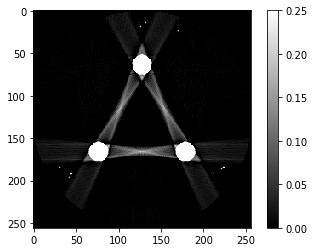

# Question 11

reproj = iradon(tmp, theta=theta, circle=True)

plt.imshow(reproj,vmin=0,vmax=0.25)

plt.colorbar()

1

<matplotlib.colorbar.Colorbar at 0x7fce5a02cd00>

# Question 12

search = np.linspace(0,1,11)

for alpha in search:

rec = out+alpha*reproj

f,ax = plt.subplots(1,2,figsize=(12,5))

ax[0].imshow(rec,vmin=0,vmax=0.5)

ax[0].set_title(alpha)

im = ax[1].imshow(img[80]-rec)

f.colorbar(im,ax=ax[1])

ax[1].set_title('Difference from ground truth')

plt.show()